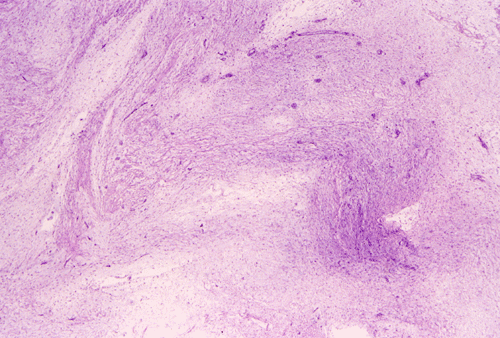

Panel A, B, and C are taken from the one area. Panel D, E, F, and G are taken from another area. Panel H and I are taken from areas with similar histologic features but distinctly separately on the same slide.

On low-magnifaction (Panel A and D), the lesional tissue appears to have generalized myomatous changes. No entrapped skeletal muscle fibers are found. The tumor cells tended to group into areas with variable cellularity that range from low- to, at most, moderate-cellularity. The hypocellular areas (Panel  B and C) contain sparsely spaced bland spindle cells in a bluish myxomatous background. The nuclei are elongated and mostly normochromatic. A few hyperchromatic nuclei are present and they are compatible with degenerative atypia (ancient change).

Islands with increased cellularity are present in some areas (Panel D, E, F, and G). These islands comprise about 30-40% of the lesional tissue. The cytologic features of the tumor cells in these areas are almost identical to that of the hypocellular areas except that the cellularity was increased. No mitotic figures are found in these areas. Focal hypervascularity are often found in areas with hypercellularity. No cellular condensation around blood vessels are noted (Panel  H and I).